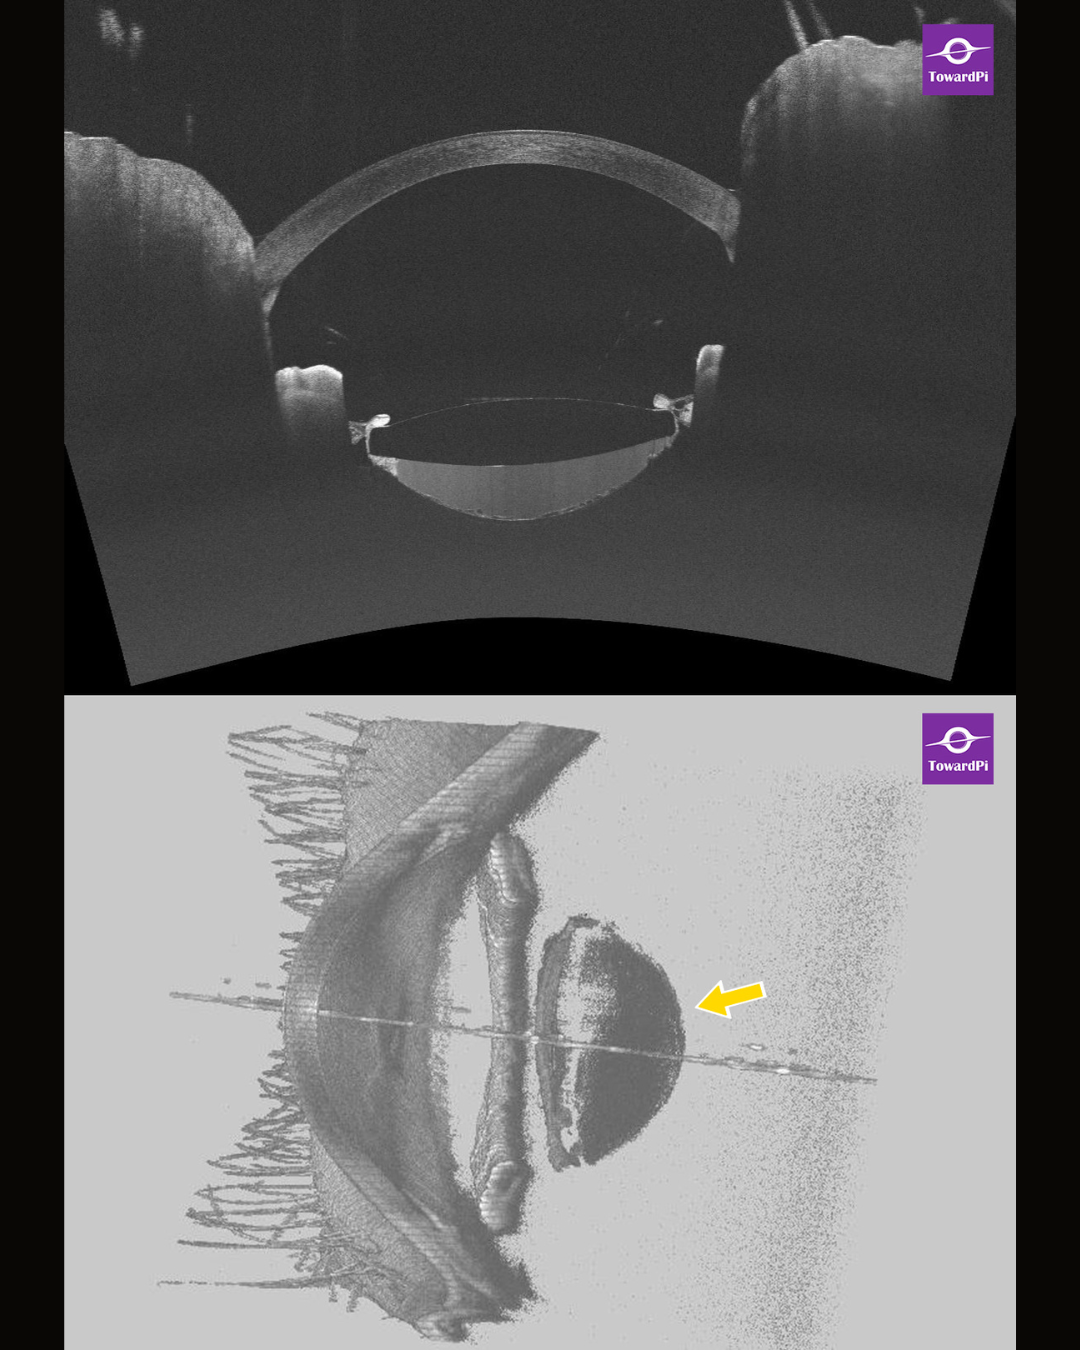

Full-range swept-source anterior segment OCT (AS-OCT) further detailed these findings, demonstrating hyperreflective fluid accumulation in the retrolental space, distension of the capsular bag, and scattered cystoid cavities on the posterior capsule (Fig. 1). Three-dimensional reconstruction of the anterior segment confirmed the presence of retrolental fluid and capsular bag distension (Fig. 1, arrow). Based on these findings, the patient was diagnosed with capsular blocking syndrome (CBS).

Fig.1